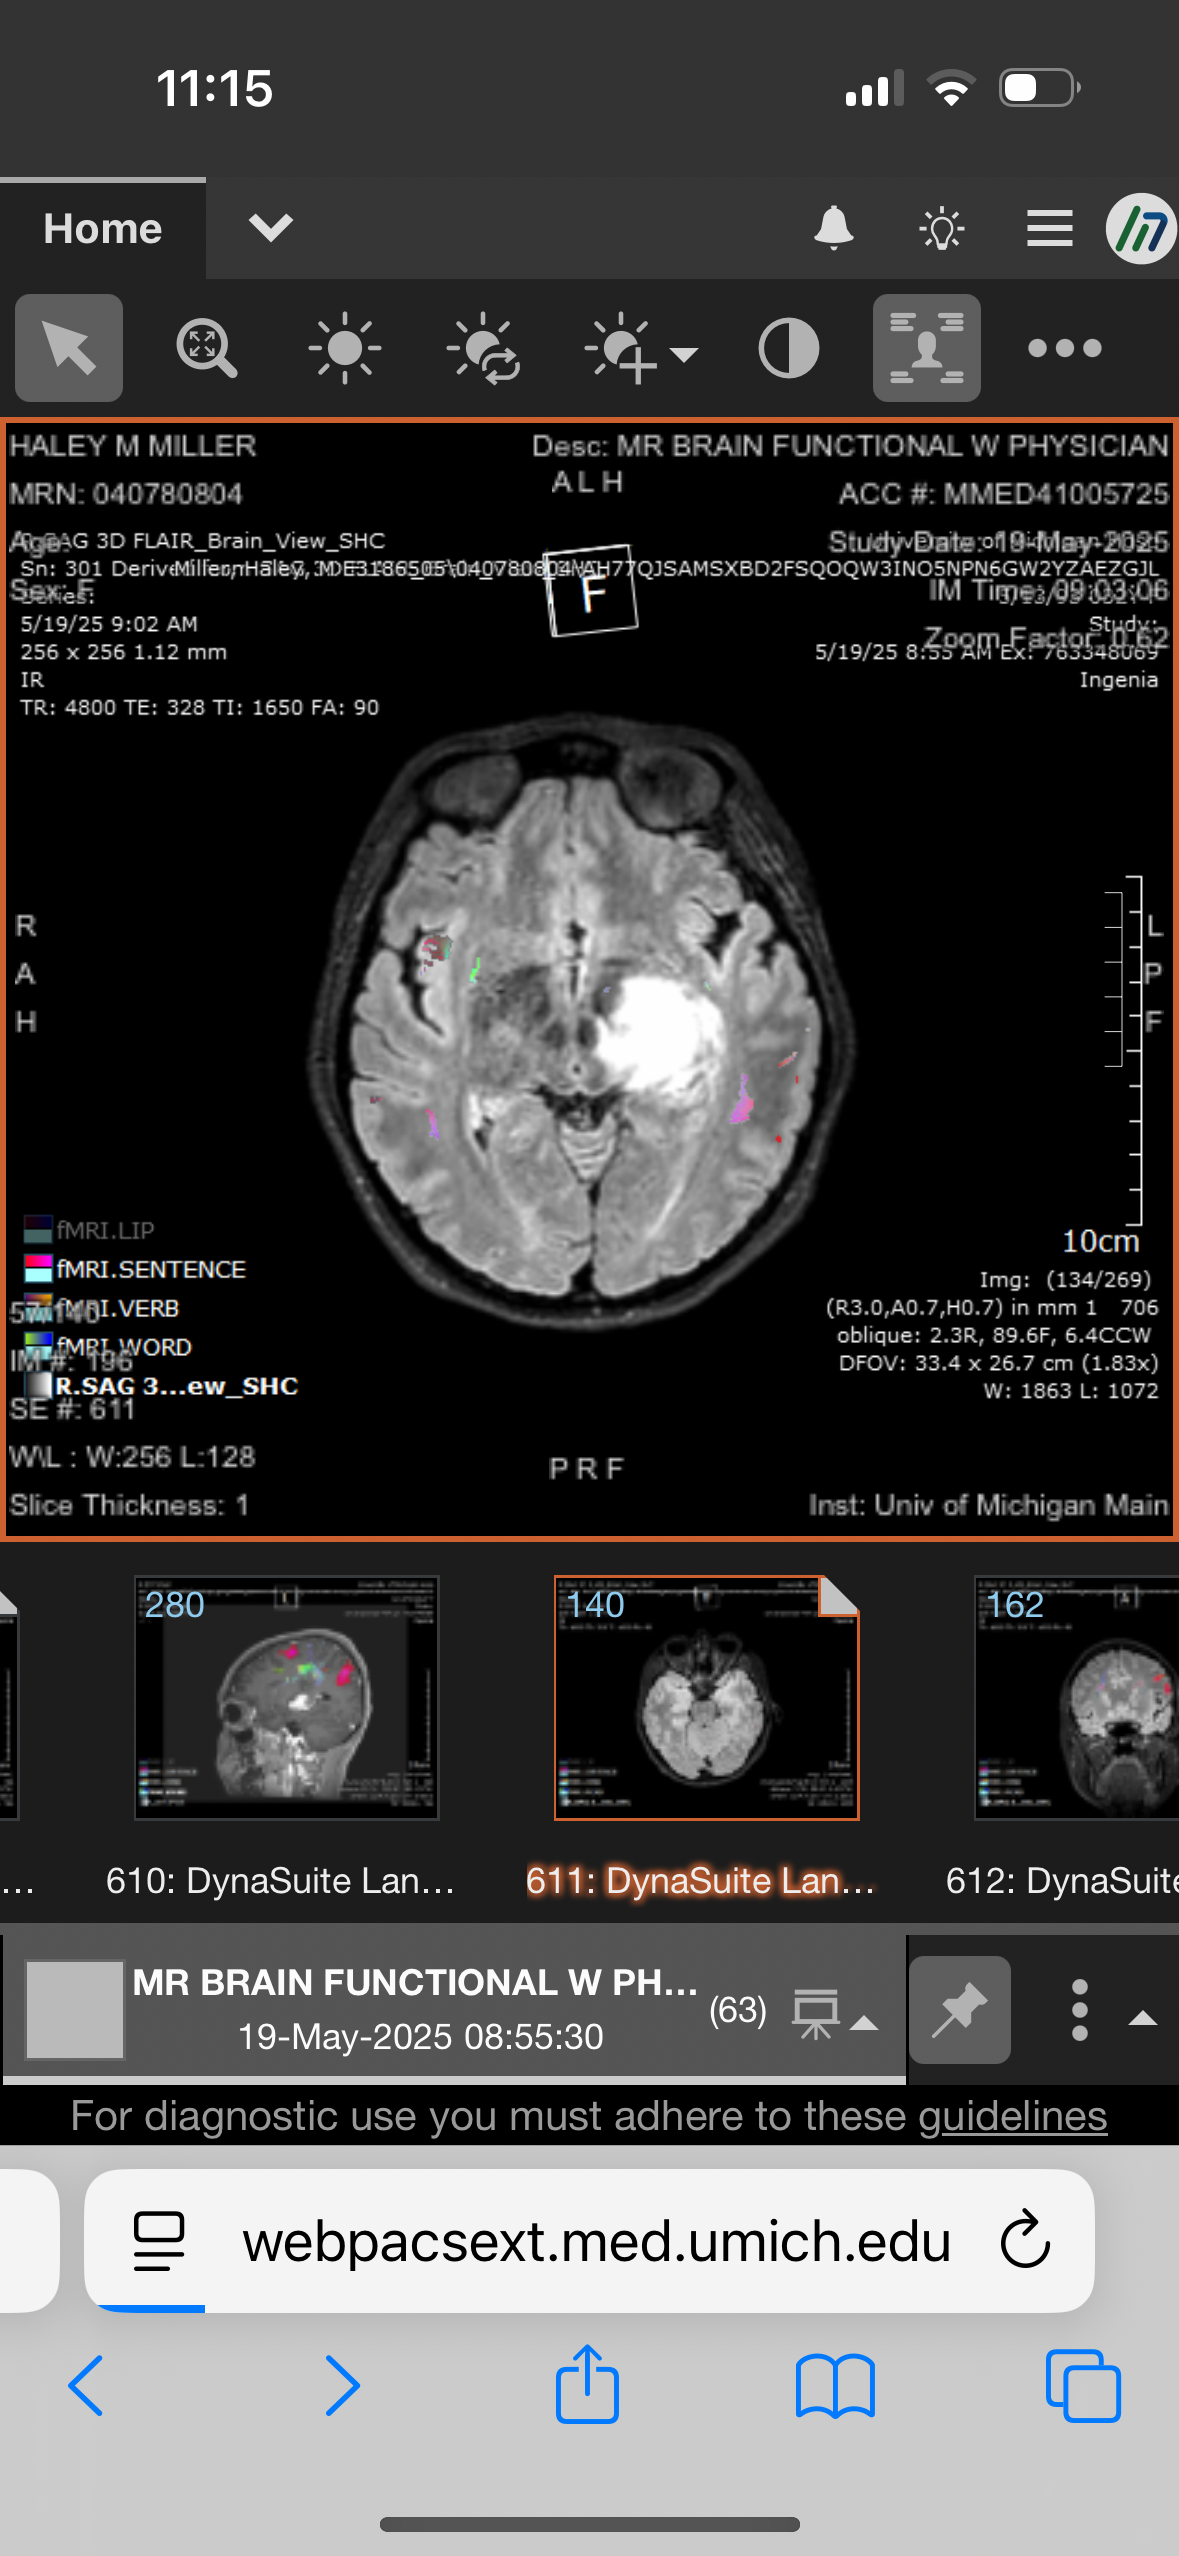

I'm reaching out on behalf of my amazing sister, who at just 32 years old is facing an incredibly difficult and frightening medical journey. For a few months now, she has been experiencing blurred vision, headaches, forgetfulness, mood changes, and anxiety. Her family doctor set her up for an MRI of the brain. On May 14th, the day after her birthday, she was diagnosed with a brain mass. The mass has significantly changed in size, ranging from as small as 2.1 cm to as big as 3.7 cm, located in the thalamus, the deep part of her brain, which doctors explained is inoperable.

Now, she has been readmitted to U of M Hospital, where she will stay for the next two weeks. During this time, her doctors will closely monitor the mass and attempt a second biopsy in hopes of getting clearer answers and determining the best course of treatment. They want to try this with no steroids for the next 2 weeks, repeat the MRI, and then go from there. With all of the scans and procedures done, they are leaning towards a lymphoma.